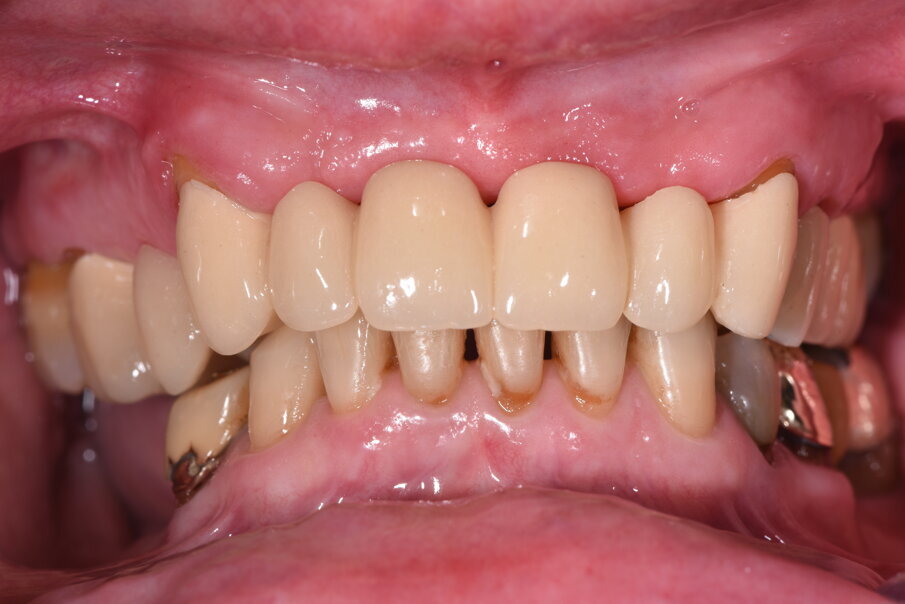

L’appuntamento successivo sancisce l’ottimizzazione dei restauri (Figg. 44, 45). Dopo il posizionamento definitivo dei restauri protesici e l’ottimizzazione dei contatti (Fig. 46) viene nuovamente registrato l’equilibrio di masticazione tramite l’uso del sincronogiografo che registra le forze muscolari confrontando i valori registrati dal momento iniziale pre-trattamento a quello con i provvisori e infine alla stabilizzazione finale, così che nel tempo si possa aver traccia dell’adattamento realizzato (Fig. 47).

Il recupero funzionale ed estetico (Figg. 48, 49) rappresentano il traguardo dopo un lungo percorso. Il condizionamento della paziente ha rappresentato un ostacolo nelle libere scelte cliniche segnando di conseguenza l’intero percorso. L’aspetto psicologico ha giocato un ruolo importante nella realizzazione del piano di trattamento, la malattia precedente e il lungo periodo di provvisorizzazione ha arrecato nella paziente un forte disagio. Talvolta quest’aspetto induce il clinico a fare dei compromessi procedurali e anche noi abbiamo cercato di ottimizzare una riabilitazione estetico funzionale correndo dei rischi procedurali a fronte di una richiesta conservativa e talvolta riduttiva nelle procedure chirurgiche. A oggi il follow-up e i controlli di igiene e di verifica della funzione è cadenzato e rigorosamente rispettato dalla paziente. A 5 anni non sono stati evidenziati problemi dei materiali impiegati né tantomeno funzionali (Figg. 50, 51).

Fig. 44_Il momento della consegna rappresenta anche un controllo che deve valutare la cementazione dei monconi l’eventuale presenza di eccessi di cemento, la lucidatura dei punti di contatto e degli spazi interpapillari.